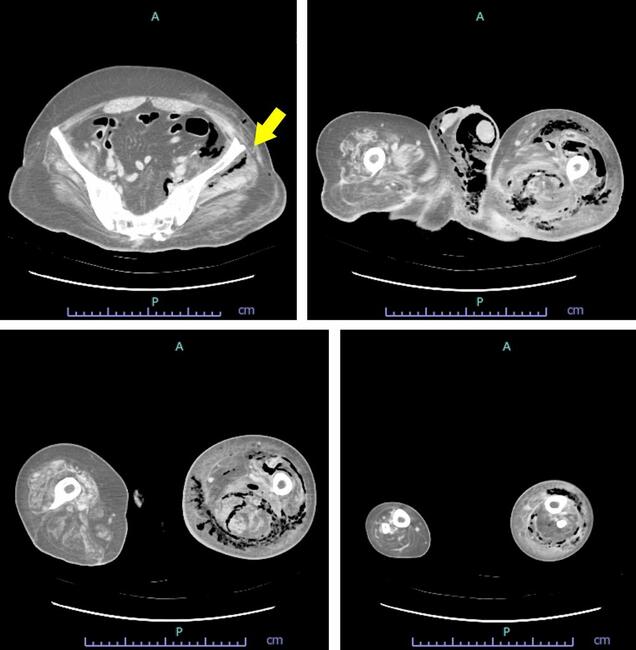

A 48-year-old man was brought to our hospital via emergency transport due to fever, altered consciousness, and swelling of the left lower limb of 2 days' duration. He had a history of lower body paresis caused by spina bifida and was previously treated at another hospital for an ischial pressure ulcer. Five years ago, he was treated for Fournier gangrene (FG). His activities of daily living (ADL) consisted of independently transferring himself to a wheelchair, standing, and walking short distances with an orthosis, and crawling indoors. Upon physical examination, the patient was noted to be in a state of pre-shock with a Glasgow Coma Scale score of 8 (E1V3M4), body temperature of 37.1ºC, blood pressure of 112/68 mm Hg, heart rate of 112 beats per minute, and an oxygen saturation of 95% (room air). His blood test results were as follows: C-reactive protein, 46.54 mg/dL; white blood cells, 17,160/μL; hemoglobin, 13.5 g/dL; hematocrit, 41.1%; sodium, 136 mmol/L; potassium, 3.2 mmol/L; creatinine, 2.32 mg/dL; glucose, 193 mg/dL; and bicarbonate, 19.2 mmol/L. Computed tomography revealed extensive gas accumulation in the perifascial, intermuscular, and intramuscular regions of the left buttock, perineum, thigh, and lower leg (Figure 1). Therefore, the diagnosis of NSTI was made.

Figure 1. Computed tomography scans showing extensive gas images in the perifascial, intermuscular, and intramuscular regions, extending down from the left buttock (arrow) to the perineum, left thigh, and left lower leg.